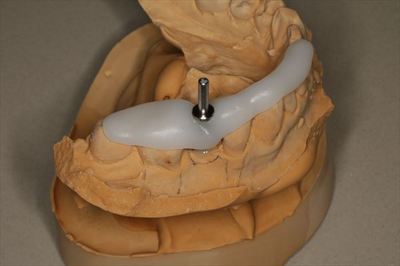

ドリルガイドであるサージカルステントを作成します。

![]()

オペ前の事前準備が整いました。